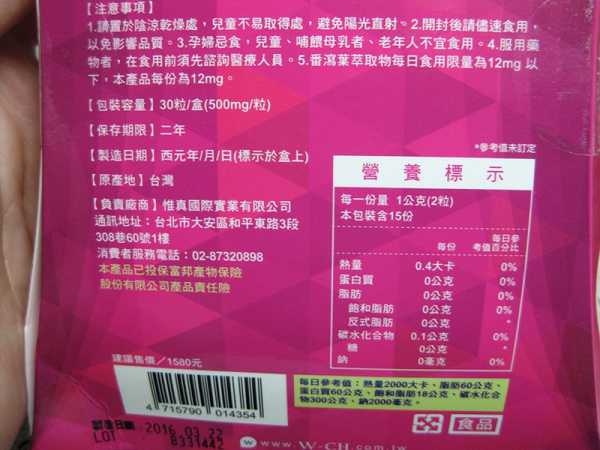

每一盒Supercut塑魔纖立塑膠囊都有三小包,每一小包有10顆膠囊

體積都不大,很適合放在包包裡帶上帶下的喔

番瀉葉萃取物每日食用限量為12mg以下,

番瀉葉萃取物每日食用限量為12mg以下,

鉻與脂肪代謝有關,有助於控制血液中的膽固醇,並有降低血壓的作用,可以預防高血壓,對降低體重也有不錯的效果。

鉻與脂肪代謝有關,有助於控制血液中的膽固醇,並有降低血壓的作用,可以預防高血壓,對降低體重也有不錯的效果。